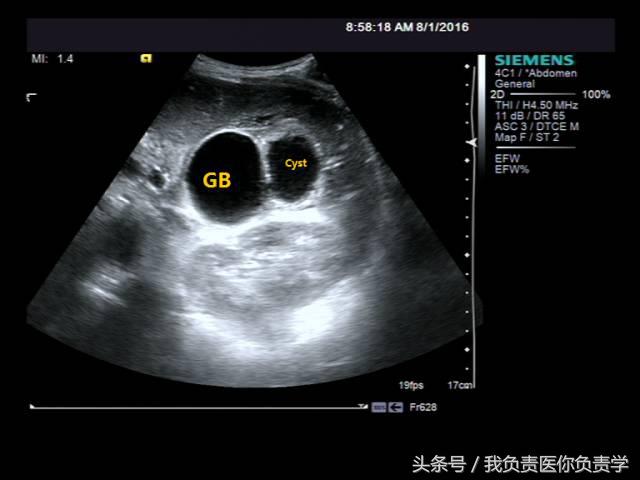

典型病例 1

患者男,64岁,因右上腹疼痛半月余就诊。查体发现右上腹部轻压痛,无发热。超声检查所见如下:

图3示胆囊与囊性回声区间隐约可见裂隙相通

图4和5为局部放大图像,可见胆囊与囊性回声区间可见直径约2mm的通道

超声检查考虑为胆囊炎合并胆囊穿孔,后经CT检查证实。